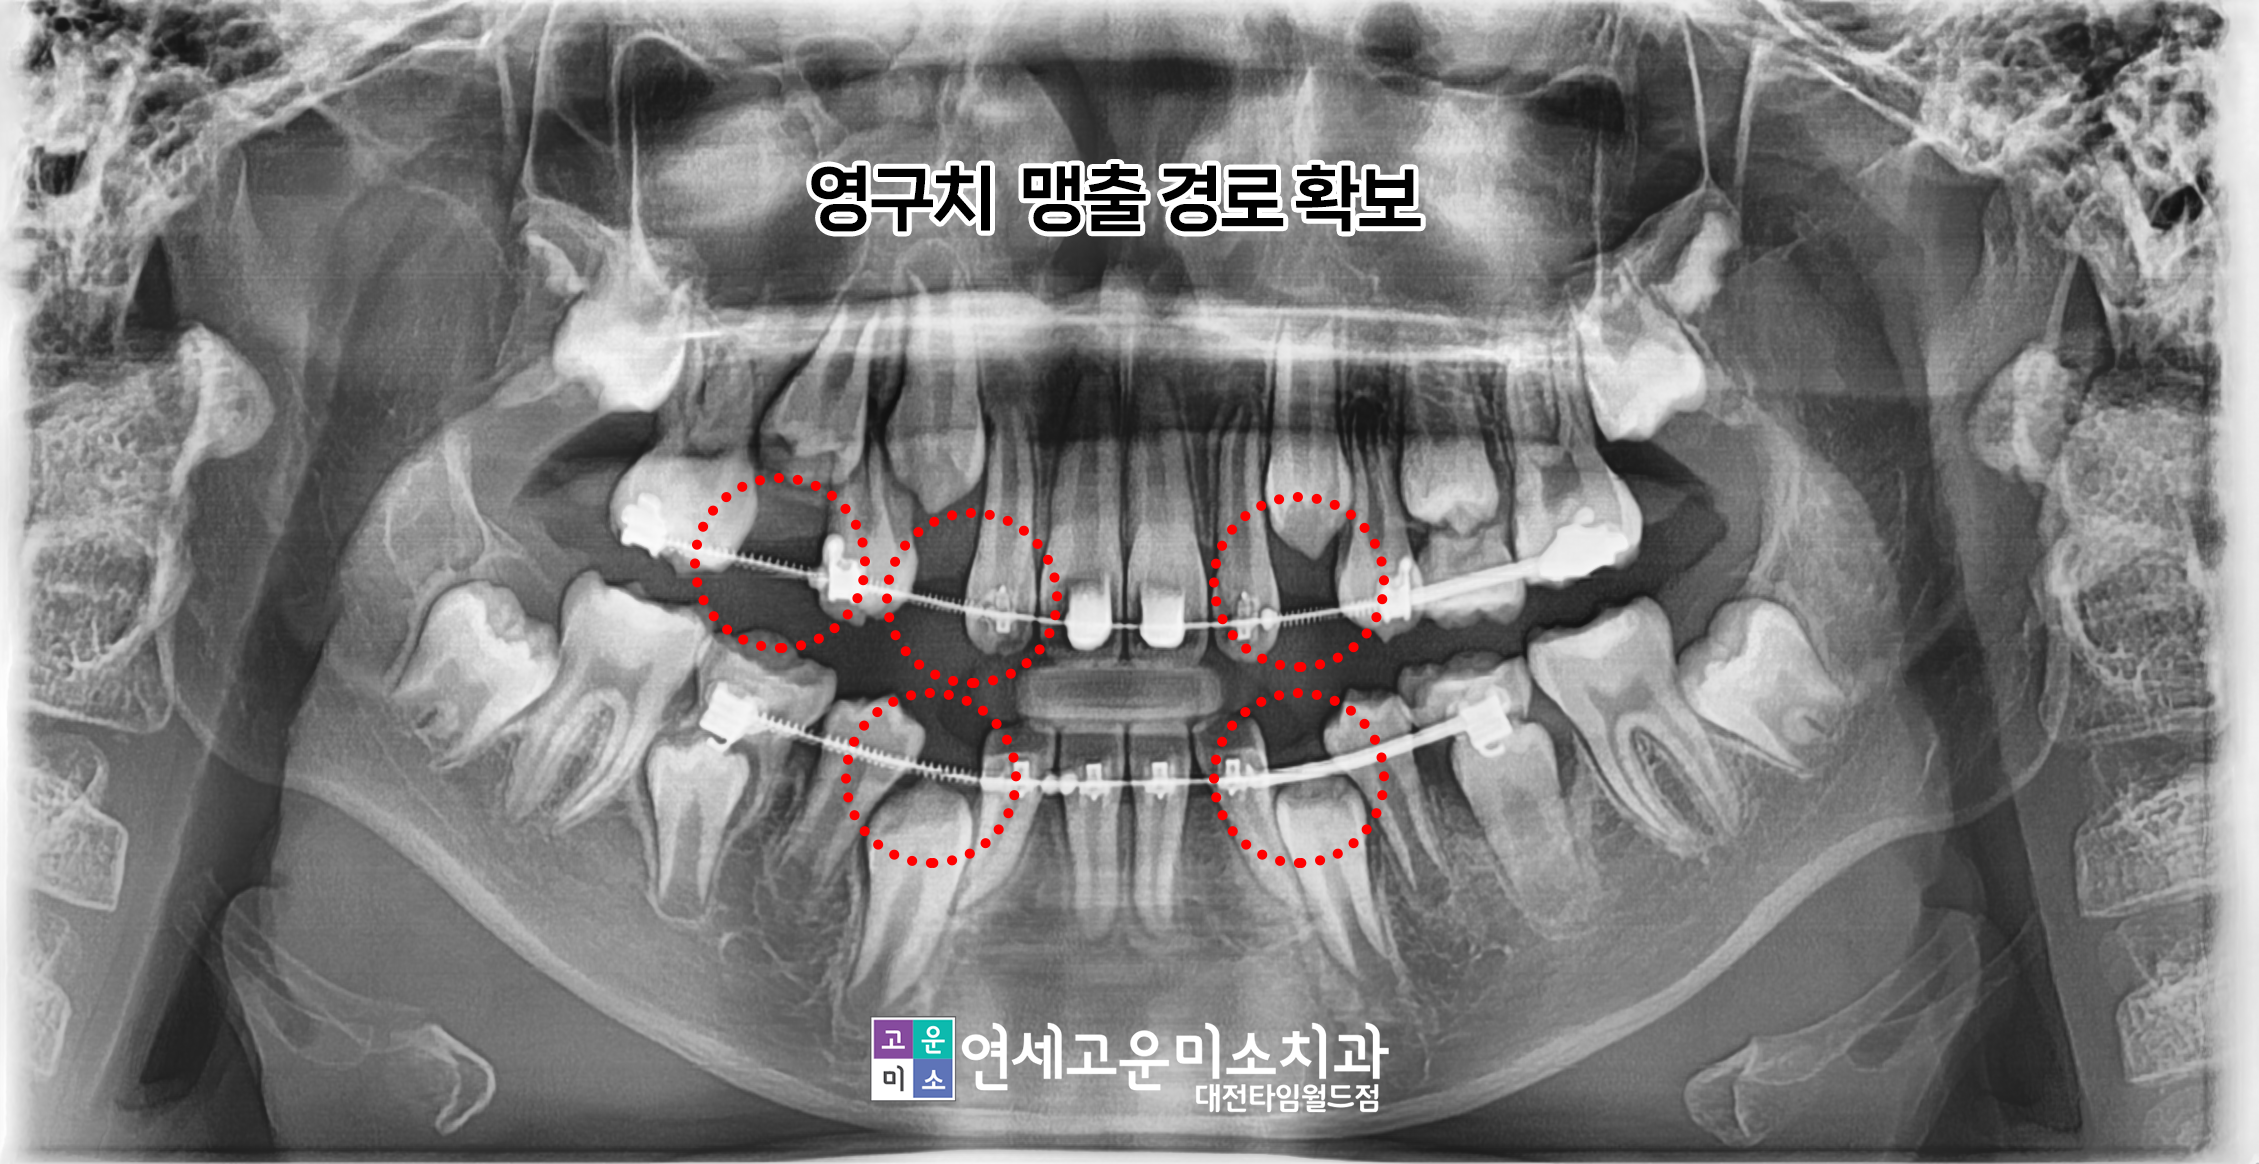

이런 경우 입이 나온 경우라면 기다렸다가

작은 어금니 4개를 빼고 교정해도 되지만

이 환자분의 경우 입이 전혀 나오지 않았기 때문에

발치 교정은 합죽이처럼 될 가능성이 있습니다.

그래서 조기에 교정을 시작하기로 결정하였고

유치가 있는 상태에서 시작하였습니다.

공간 확보를 위하여 유치도 활용하였고

공간이 생기고 있는 것을 확인할 수 있습니다.